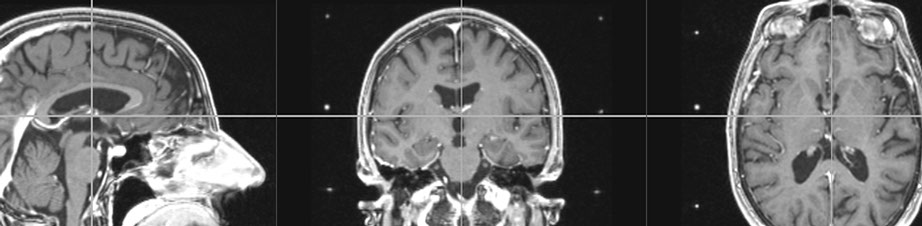

De beeldanalysesoftware met MRI-beelden helpt om te bepalen hoe de probe tussen kritieke hersenstructuren door precies in het doelgebied kan worden gestoken. De software helpt om de metingen tijdens operaties te interpreteren. Tot slot is er het afstellen van de pulsgenerator, doordat de Sapiens-probe ook kan meten, kan die straks met de 64 elektrodes de stimulatie gericht sturen. Het systeem visualiseert het doelgebied en de ladingswolk.